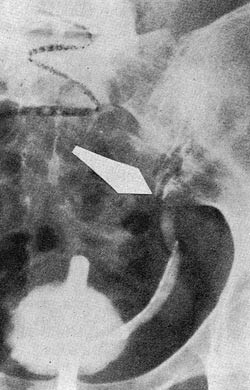

Preparatet viste et hasselnøttstort vevstykke med et hvitt sentrum og en brunfarget bord. Tumor omsluttet hele ureter så det bare var en trådtynn passasje. Det mikroskopiske bildet viser et udiffrensiert carcinom utgått fra overgangsepitel, med infiltrerende vekst og atskillig kjernevariasjon (fig 3, mikrofoto: Det Norske Radiumhospital, Laboratorium for patologi).